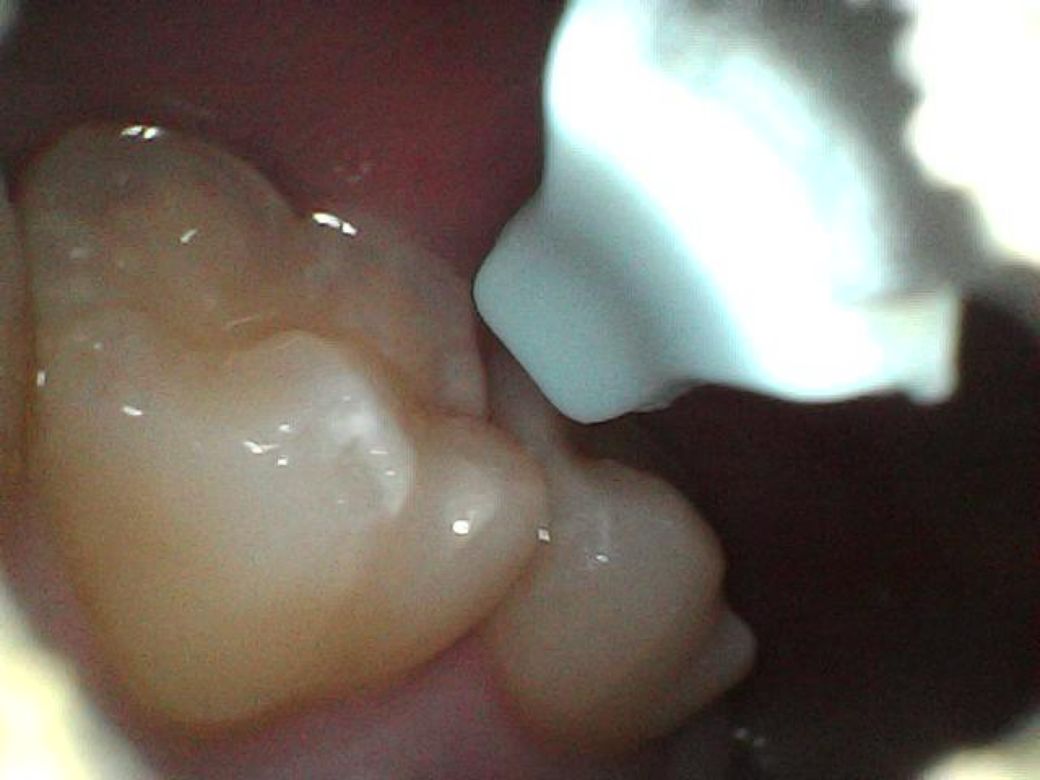

어제 아침, 오늘 아침 이틀동안 찍은 사진들인데 이거 혹시 사진으로 뭔지 구분이 가능할까요?

어제보다 크기가 좀 줄어든 느낌이라 치석인가

싶어 다행은 한데..

명절이라 치과도 안하고 ㅎㅎ..

처음 두장이 어제, 나머지가 오늘 사진입니다

오늘

• 3번 째 사진

• 4번 째 사진